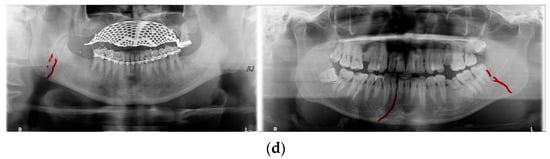

In Table 6, the parameters used for training are indicated, and in Figure 11, Figure 12 and Figure 13, the results of the doctor’s diagnosis, Mask R-CNN, YOLOv4, U-Net, LAT YOLOv4, and U-Net withYOLOv4 are compared. Figure 11 illustrates fractures in the angle and condylar regions, and in Mask R-CNN, the symphysis is misdiagnosed as a fracture. In Figure 12, the Mask R-CNN misdiagnoses the symphysis as a fracture, the result of the fact that the YOLOv4 module has better performance detecting angle fractures rather than does the LAT YOLOv4, as shown in Figure 12c,e. In short, the LAT-processed image does not always have the advantage of better revealing fractures compared with the normal panoramic radiograph.

Figure 11.

The comparison of mandibular fracture detection: (a) oral and maxillofacial radiologist, (b) Mask R-CNN (with colored polygons and boxes), (c) YOLOv4, (d) U-Net (with a red line), (e) LAT YOLOv4 (with red boxes), and (f) U-Net with LAT YOLOv4 (with a red box and lines).

Figure 12.

The comparison of mandibular fracture detection: (a) oral and maxillofacial radiologist, (b) Mask R-CNN (with colored polygons and boxes), (c) YOLOv4 (with a red box), (d) U-Net (with a red line), (e) LAT YOLOv4, and (f) U-Net with LAT YOLOv4 (with a red line).

Figure 13.

The comparison of mandibular fracture detection: (a) oral and maxillofacial radiologist, (b) Mask R-CNN (with colored polygons and boxes), (c) YOLOv4 (with a red box), (d) U-Net (with red lines), (e) LAT YOLOv4 (with red boxes), and (f) U-Net with LAT YOLOv4 (with a red box and lines).

In Figure 13, the ramus is misdiagnosed as a fracture. Therefore, Mask R-CNN had the lowest precision score because the misdiagnosis rate was higher than that of the other modules (Figure 16). The YOLO module has a low misdiagnosis rate, while the ‘undiagnosis’ rate is high; therefore, the F1 score is low owing to the ’undiagnosis’ rate. As shown in Figure 11, Figure 12 and Figure 13, YOLOv4 and LAT YOLOv4 have strong advantages over location information; therefore, they tend to detect well in the condyle region, that is, the side fracture, while they tend to detect poorly in the symphysis, body, and angle regions, where location information is ambiguous. Unlike Mask R-CNN and YOLO, U-Net is an image segmentation deep learning network, not an object detection deep learning network and labels mandibular fractures. U-Net marks fractures as lines on the label during training; however, it is difficult to label dislocated fractures, such as condyle fractures (Figure 11). Therefore, in the U-Net module, the side fracture was not diagnosed or misdiagnosed, and the precision-recall score was lower than that of the YOLO modules. It was judged that if the two deep learning networks are used together, the shortcomings of YOLO and U-Net complement each other and help improve mandibular fracture performance. In the proposed module, duplicate boxes that occurred in LAT YOLOv4 were removed before merging with the U-Net. In the proposed U-Net with LAT YOLOv4, the precision score was reduced; however, many ‘undiagnoses’ were eliminated; therefore, the recall score was increased, and it can be observed that the overall F1 score improved the performance by more than 90%.